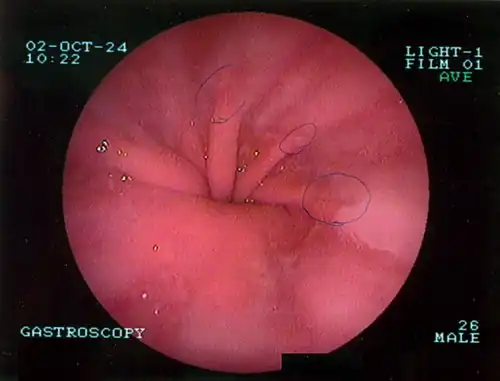

The diagnosis of a hiatal hernia is typically made through an upper GI series, endoscopy, high resolution manometry, esophageal pH monitoring, and computed tomography (CT). Barium swallow, as in the upper GI series, allows the size, location, stricture, and stenosis of oesophagus to be seen. It can also evaluate the oesophageal movements. Endoscopy can analyse the esophageal internal surface for erosions, ulcers, and tumours.

Upper GI endoscopy depicting hiatal hernia

Upper GI endoscopy depicting hiatal hernia -